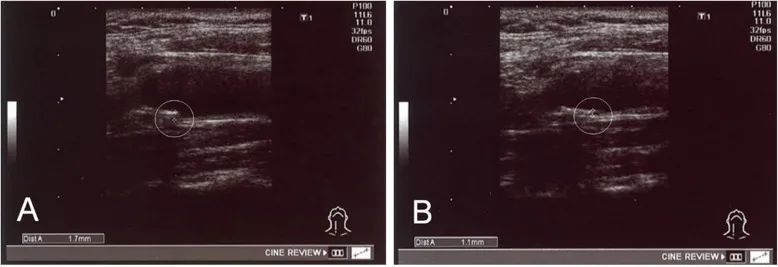

△经过干细胞给药,一名患者内膜中膜厚度 (IMT)从 1.7 毫米降至 1.1 毫米